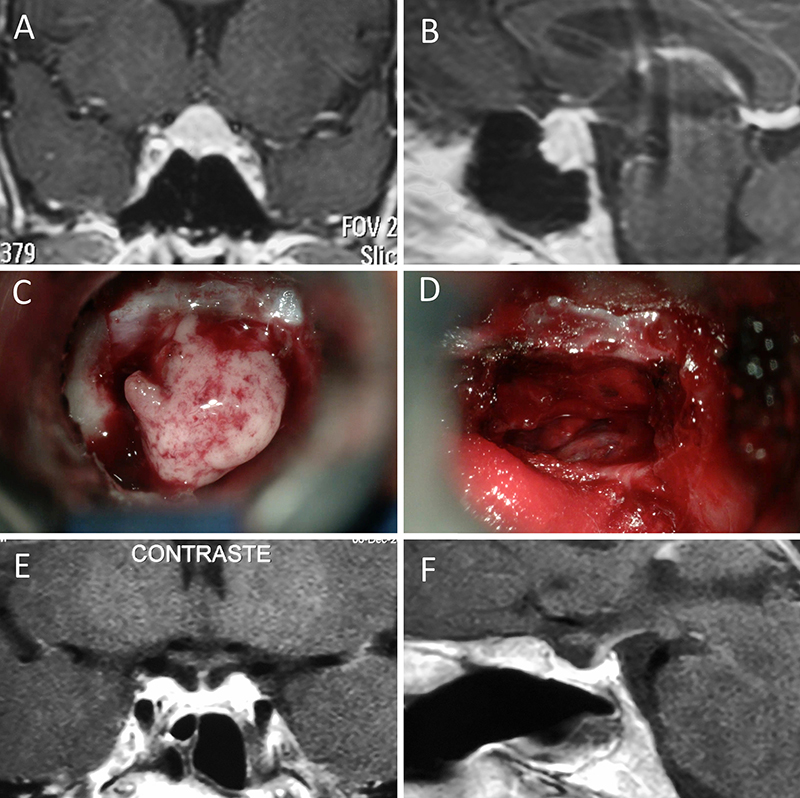

Figura 14: Prolactinoma en un hombre de 32 años. Sufrió un cuadro de apoplejía pituitaria durante su tratamiento con cabergolina. Fue intervenido quirúrgicamente, evolucionando con normoprolactinemia. A-B: RM preoperatoria; C-D: intraoperatorio; E-F: RM postoperatoria.

Figura 15: Prolactinoma en una mujer de 19 años. Cursó con cuadro de resistencia a la cabergolina. Se decidió tratamiento quirúrgico y evolucionó con remisión bioquímica. A-B: RM preoperatoria; C-D: intraoperatorio; E-F: RM postoperatoria.